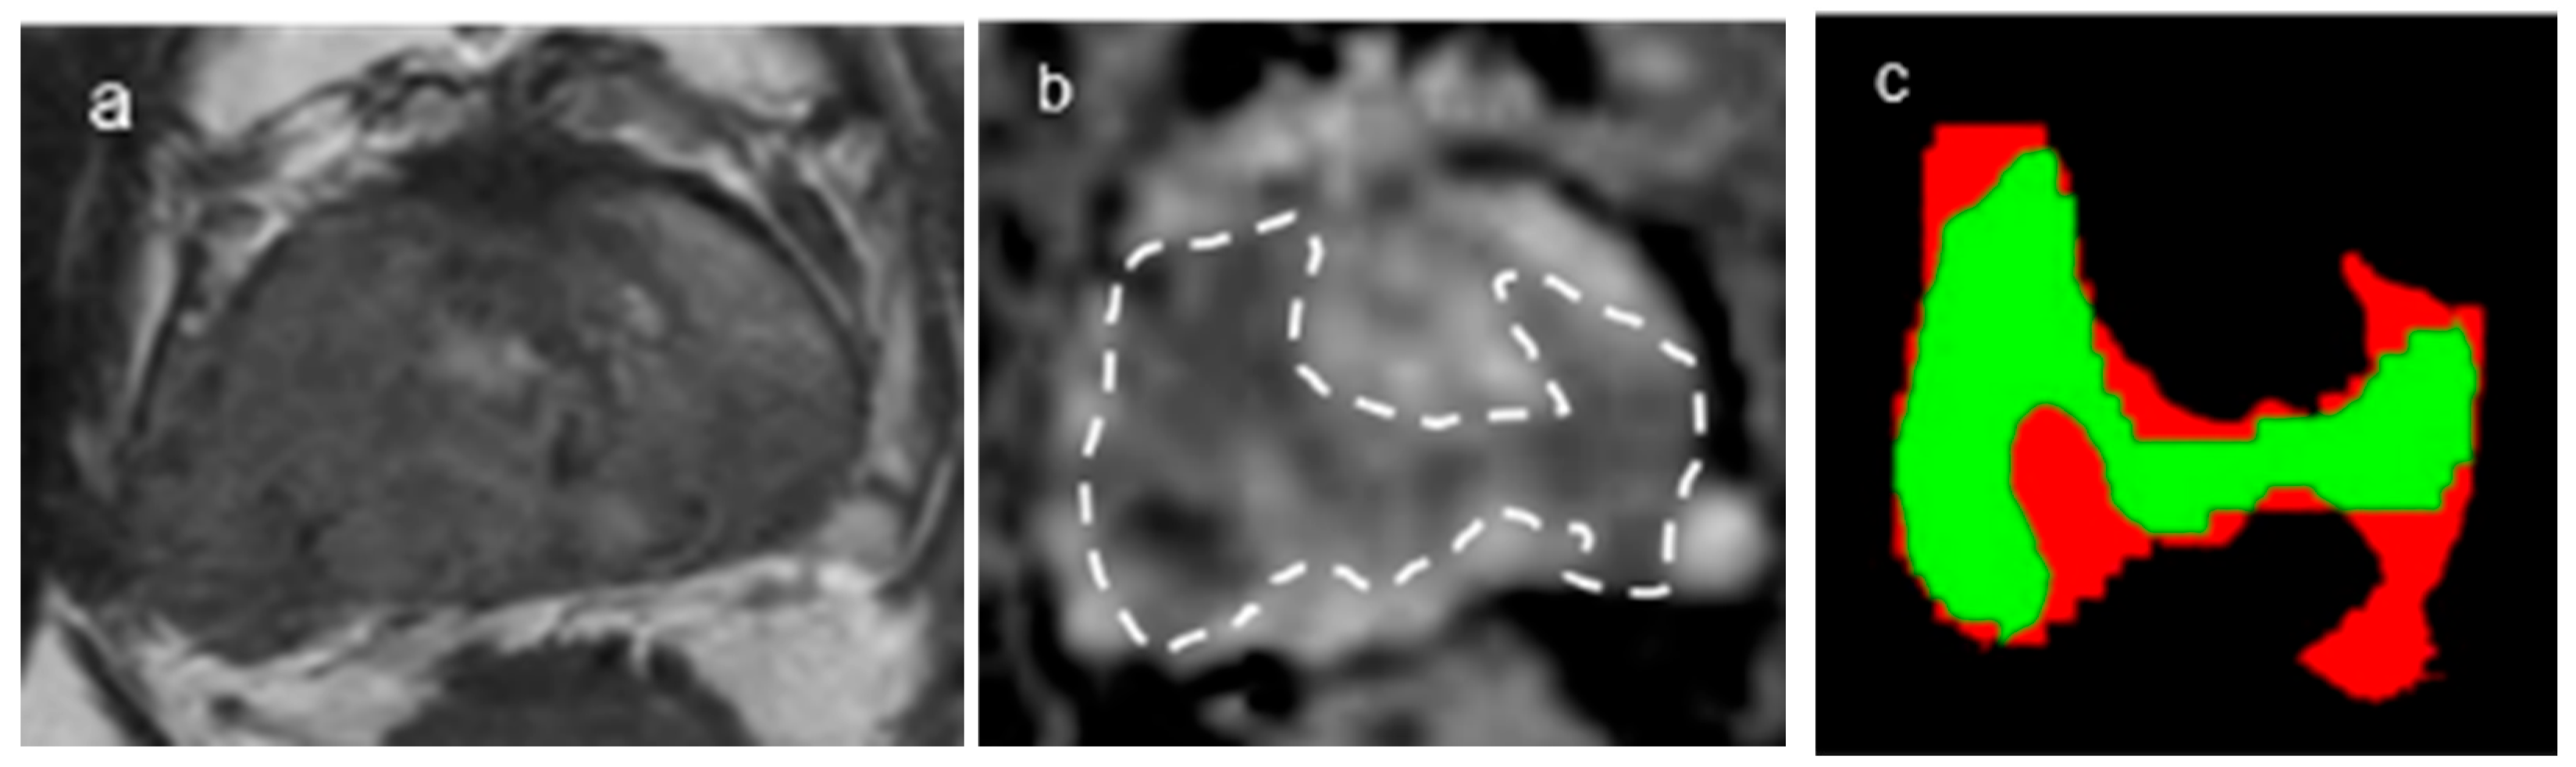

2.4. DL Architecture for Tumor and Gland Segmentation

2.5. DL Architecture for Tumor Classification